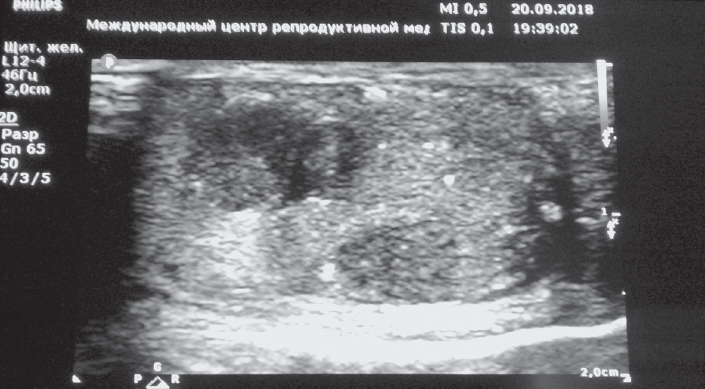

一名显示了超声征象睾丸肿瘤的男子在泌尿肿瘤科住院了(见图1),其进行了左侧睾丸切除术,随后的手术后组织病理学研究显示了左侧睾丸混合生发性肿瘤,以精原细胞瘤和成熟的青春期后畸胎瘤合并小管内生殖细胞瘤形成(рТ1)。

图 1 双侧睾丸微石症男性左侧睾丸的超声检查。显示了睾 丸肿瘤的多个微晶及不均匀回声结构